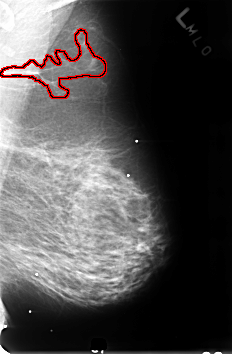

B_3242_1.LEFT_MLO

LEFT_MLO LINES 4600 PIXELS_PER_LINE 3016 BITS_PER_PIXEL 12 RESOLUTION 50 OVERLAY

FILE: B_3242_1.LEFT_MLO.OVERLAY

TOTAL_ABNORMALITIES 1

ABNORMALITY 1

LESION_TYPE MASS SHAPE ASYMMETRIC_BREAST_TISSUE MARGINS N/A

ASSESSMENT 2

SUBTLETY 5

PATHOLOGY BENIGN_WITHOUT_CALLBACK

TOTAL_OUTLINES 1

BOUNDARY